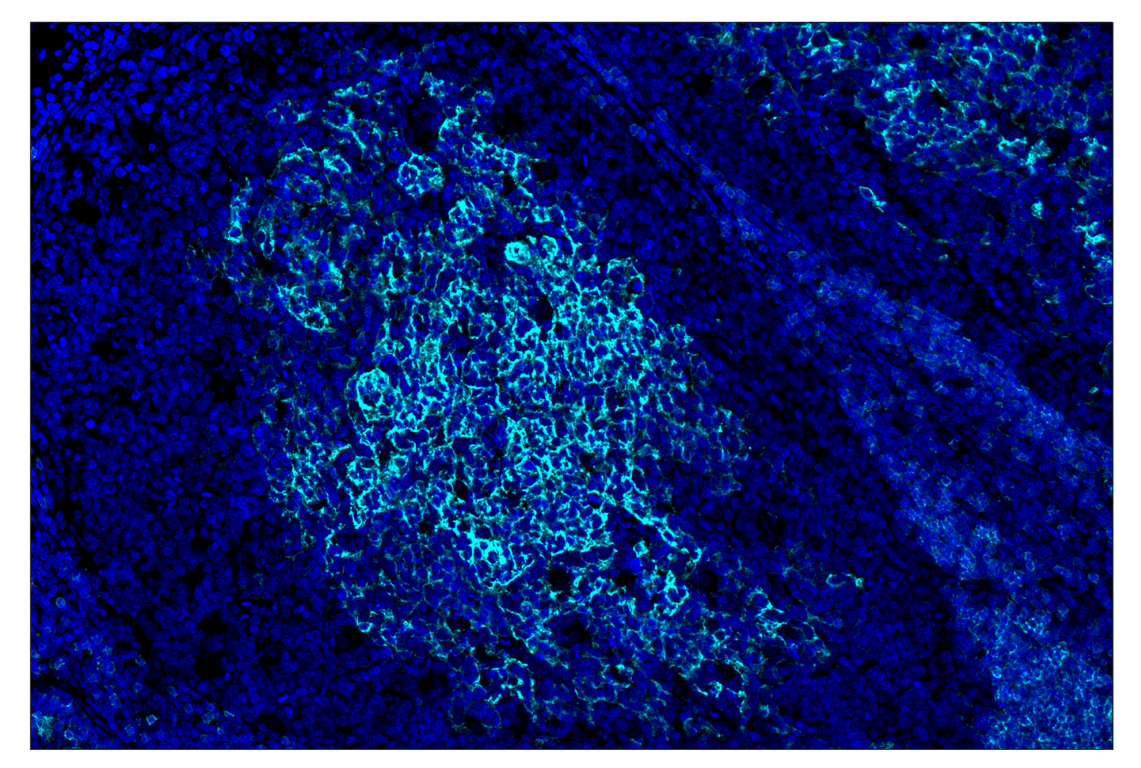

Figure 1. All antibodies in your plex size of choice (3-8 maximum unique oligo-conjugated antibodies) are added in cocktail in one primary incubation step. Complementary oligos with fluorescent dyes (channels: 488, 594, 647, and 750) amplify the signal of up to 4 oligo-conjugated antibodies in the first round of imaging by building oligo-fluorophore constructs attached to the antibody. If the plex size is greater than 4, the first round of oligos and fluorophores are gently removed, and a second round of amplification is performed to visualize up to 4 additional oligo-conjugated antibodies; the complementary oligo system and the use of the fluorophore removal process enables a second round of antibodies to be amplified from the same substrate, without cross-reactivity. The 2 images are then aligned and fused computationally with either proprietary or open-source software to generate an image consisting of up to 8 targets.